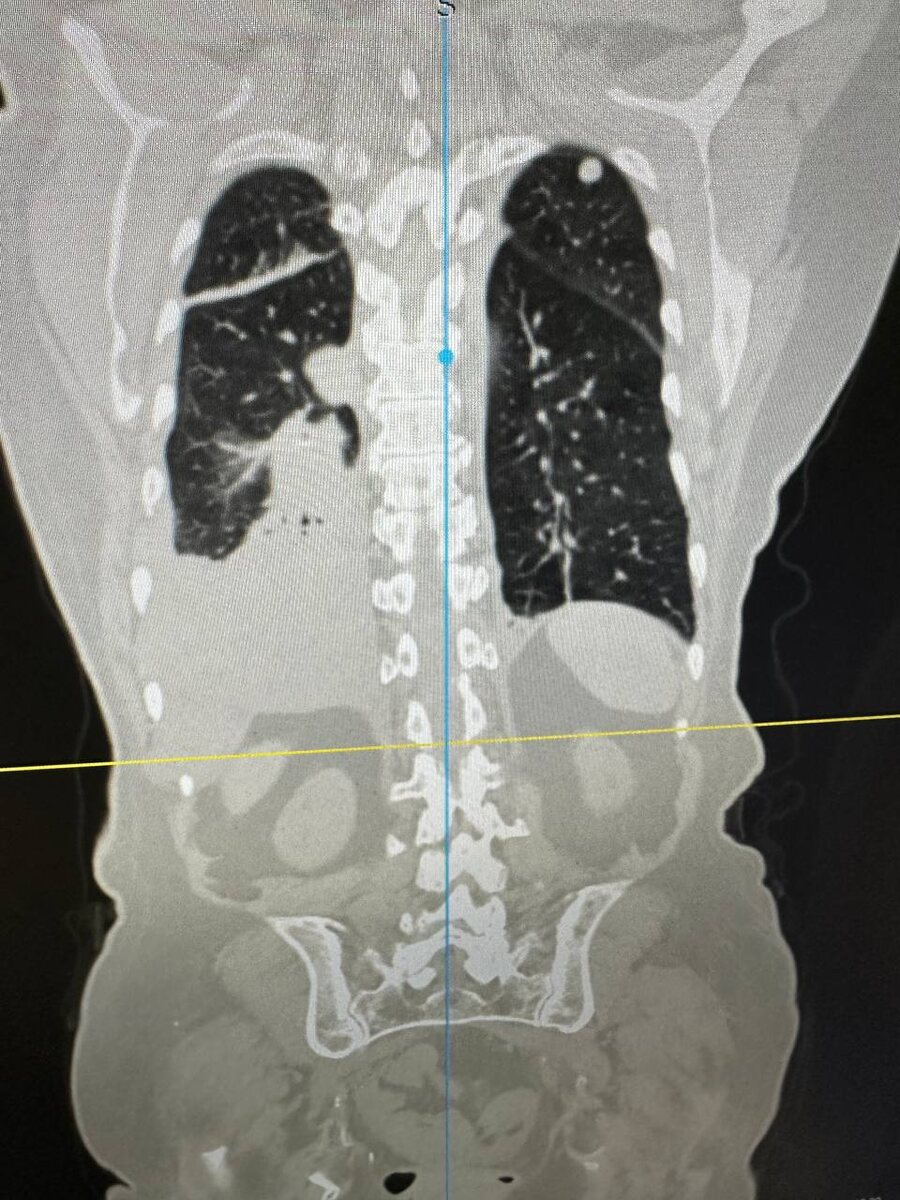

КТ - метастазы в лёгком.